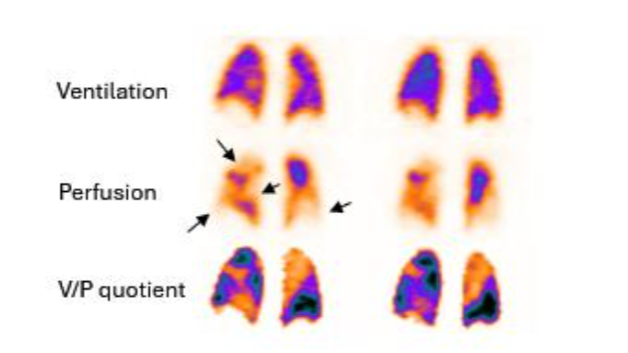

Scintigrafia di ventilazione/perfusione (V/Q SPECT)

Il protocollo ventilazione/perfusione offre una risoluzione di contrasto significativamente superiore, permettendo di identificare piccoli difetti sub-segmentali che verrebbero “mascherati” dal parenchima sano sovrastante nelle immagini planari (effetto “shine-through“). Il paziente viene posizionato in decubito supino per uniformare la distribuzione della perfusione. L’acquisizione della ventilazione precede solitamente quella della perfusione se si utilizza lo stesso isotopo (99mTc), per evitare che l’attività della perfusione (maggiore) interferisca con quella della ventilazione.

Immagini di perfusione (in alto) e ventilazione (in basso) in proiezione obliqua posteriore destra, che mostrano difetti a cuneo in un paziente con EP.